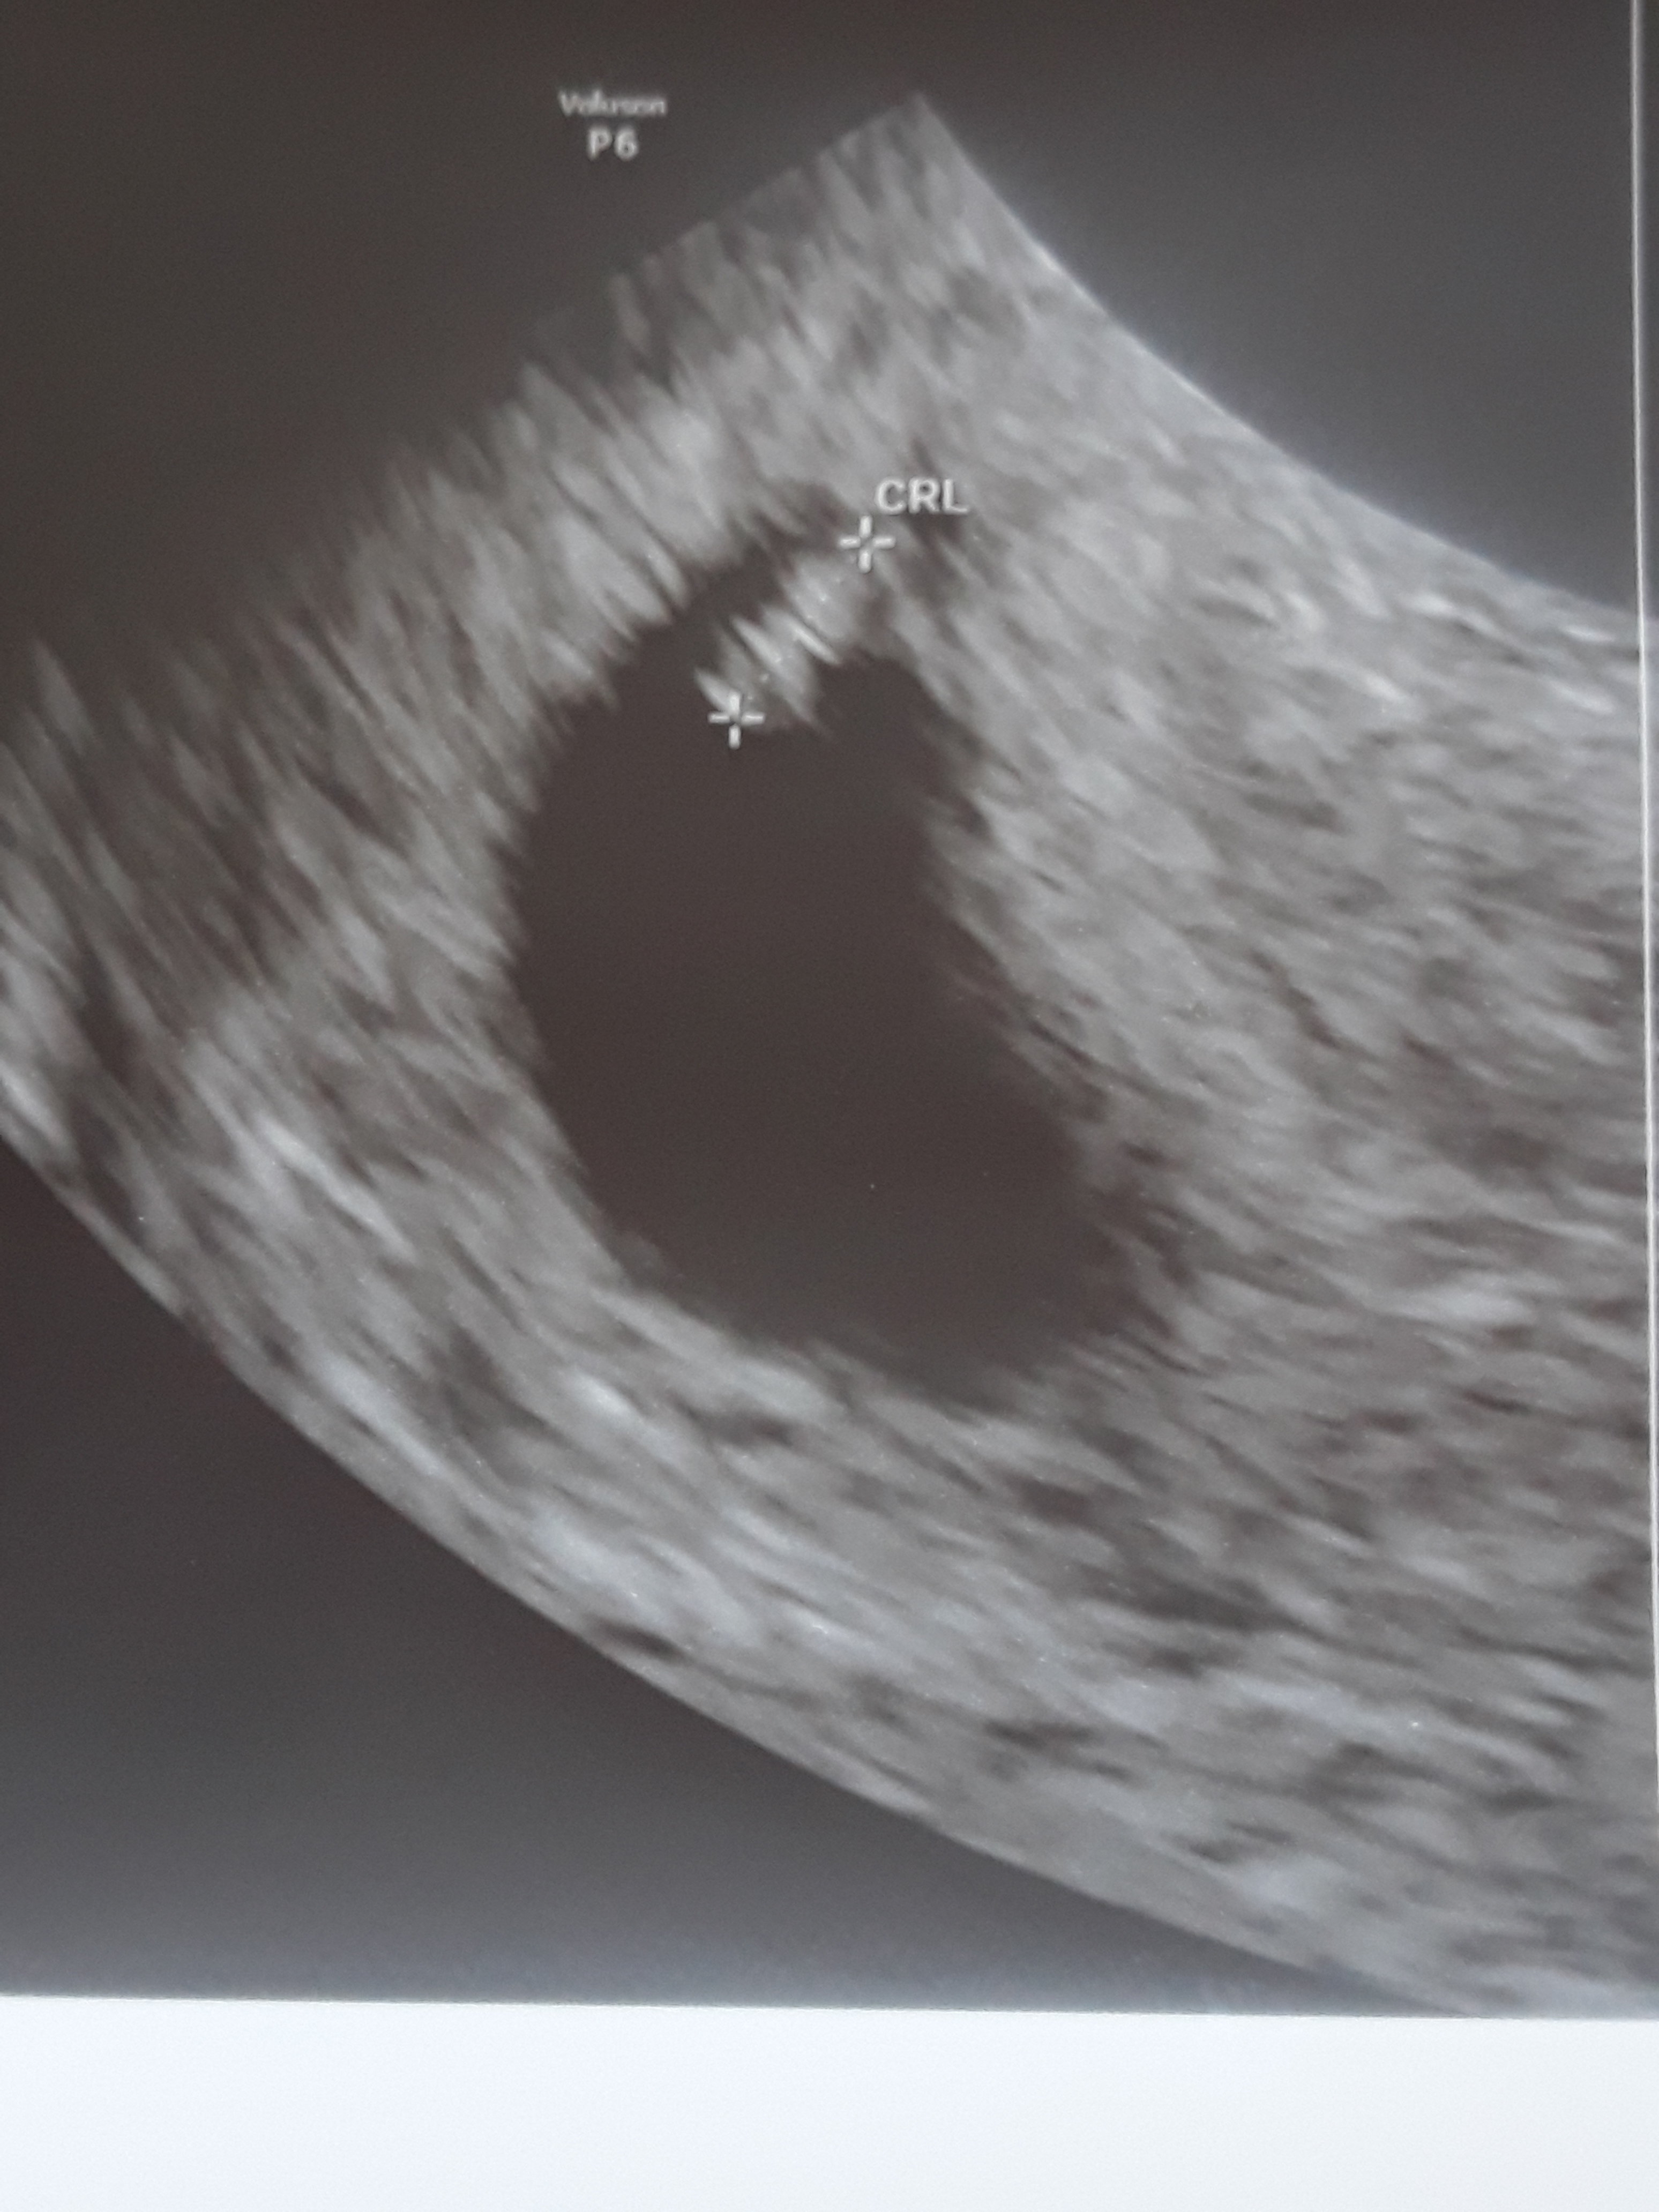

Dzidziuś jest ma 5.6mm serducho bije tylko mam torbiel na jajniku i muszę więcej wypoczywać szczesliwa jestem kontrola za 2 tyg

20190417_171523.jpg